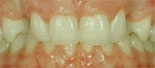

Utrymmesanomalier

Utrymmesanomlier före behandling Utrymmesanomalier efter behandling

Före behandling av utrymmesanomali (trångställning) Efter behandling av utrymmesanomali (trångställning)

Utrymmesproblem beror på att det antingen saknas tänder, eller att det finns för många, alternativt att käkarna är för små eller för stora. Tänder kan vara trångställda, beroende på att det är ont om plats i käkbenet. Det omvända problemet finns också, det vill säga att tänderna är glesställda så ett mellanrum bildas.